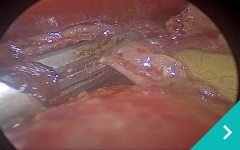

ミニマム創内視鏡下手術は腹腔鏡だけでは対処ができないような手術の際に、お腹にラッププロテクターという器具を設置して行う腹腔鏡と開腹手術を組み合わせた手術です。